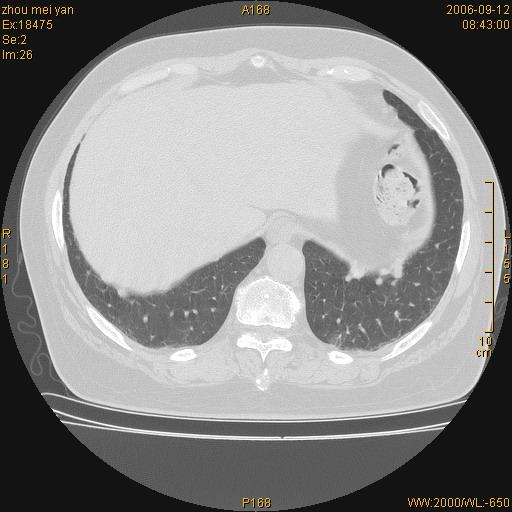

患者、女、55岁。因心率失常住院检查ct发现胸部多发结节。腹部b超肝、胆、胰、脾、肾、子宫附件未见异常。无结核病史,无粉尘接触史。请大家来会诊。谢谢!

病变位于胸膜,多发结节,边界清楚,内见小结节状钙化。其它未见异常。

双侧胸膜多发结节,形态不规则,边缘较清楚,每一个结节中心似乎都有钙化点的特征,与胸膜广基相切。临床无结核病史,无粉尘接触史。

影像表现十分有特点:双侧肋胸膜及膈胸膜广泛散在分布大小在2至6mm左右,较大病灶中心可见钙化。

考虑恶性胸膜间皮瘤可能性大,病灶位于胸膜,以宽基地与胸膜相连,呈结节样改变,部分病灶内可见点状钙化影。请各位老师多多指导!

双侧肋胸膜及膈胸膜广泛散在分布大小不等结节影,较大病灶中心可见钙化。